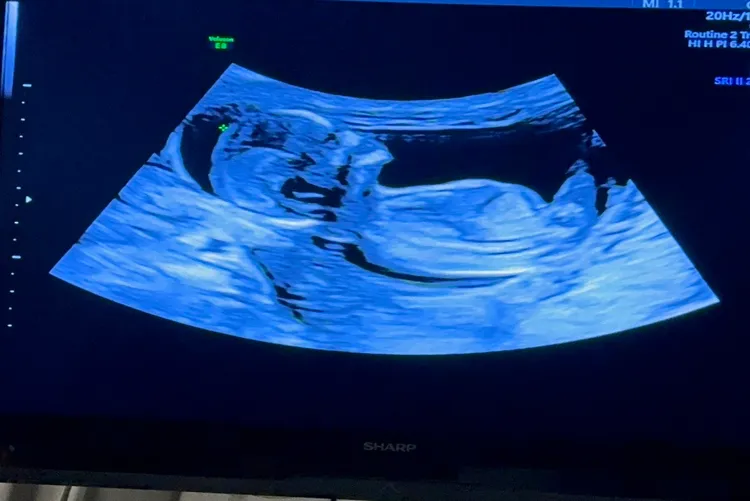

劉香慈2016年嫁給永鴻國際生技總經理鍾威凱,生了2個兒子Teddy、Enzo,第3胎性別備受關注。劉香慈回應《壹蘋新聞網》:「醫生把性別的信封交給我妹(劉方慈),她說她看完尖叫,但不知道是因為又是兒子,還是終於懷上女兒而尖叫?」答案將在之後的性別趴揭曉。

劉香慈今出席宣導施打流感活動,她透露懷孕初期跟老公到東京參加忘年會,夫妻倆連2天每天散步,步數高達2萬步,結果她晚上就大出血,躺在床上1整天才止血。回台灣就診,醫生指她「太累了」,不宜運動過量。上週到東京結果又染上流感,今天受訪時鼻音明顯。

身高171公分的劉香慈重了4公斤,約莫56公斤,懷孕是意外?她說:「是!設計好的也不一定會來,這是個禮物。」去年11月出席民視實境秀《鬥陣大廟埕》時被問第3胎,她答:「如果真的要來,我舉雙手擁抱他(她)。」沒想到孩子還真的就來了。只是身邊朋友聽聞她再懷孕,都驚呼:「妳好有勇氣哦。」而2個兒子還不知道很快就要有弟弟或妹妹降臨。

劉香慈去年陪老公出席「永鴻生技」掛牌興櫃法人說明會,她大讚另一半很拚很努力,預計今年3月股票上市,而他得知老婆懷孕也極有成就感,劉香慈說:「家中長輩也都超開心。」預產期就在今年暑假,目前就是專心待產,也依舊打算自然產。